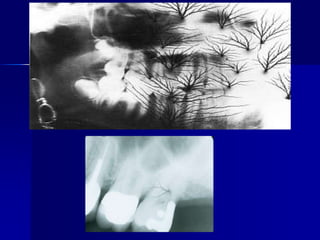

PID alignment artifactTechnique & Projection errorsa. Patient preparation errorRadiopaque artifactDental appliances, body piercings, jewelry & eye glasses left in the mouth during exposure will appear as radiopaque artifact superimposed over the dental image. Correction: all this items should be removed before placing of the film.

Technique & Projection errorsa. Patient preparation errorBlurred imageMovement of the film, patient or X-ray tube head during exposure will result in a blurred image.Correction: the operator should explain for the patient & remind him to remain motionless during exposure.

Technique & Projection errorsa. Patient preparation error:Pressure markPressure from the incisal edge & cusps of the teeth (mostly in the pediatric occlusal radiograph).May appear black or white.Correction: ask the patient to bite gently.

Static electricityProcessing errorsChemical errorsReticulationWhen the film subjected to a sudden temperature changes between the developer and water.Appear as cracked film.

Processing errorsChemical errorsBlack spot or patchDeveloper contamination before immersion into the developer solution.

Processing errorsChemical errorsBlack lineDeveloper contamination processing hanger clipsDirty roller in automatic processor

Processing errorsChemical errorsWhite spot or patchContamination with fixer before processing

Processing errorsChemical errorsYellowish brown discolorationExhausted solution or insufficient rinsing